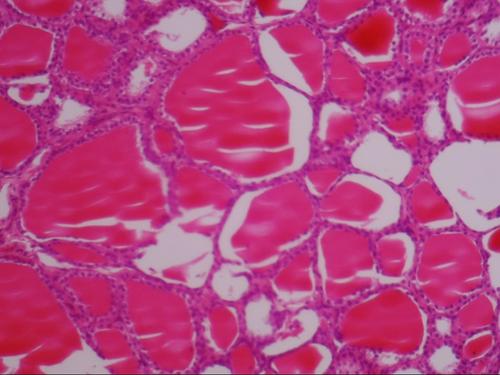

21世纪以来,本课程秉持“加强学生素养培养”的教学指导思想,积极探索全新的教学改革模式,并取得了不错的成果,有效推动了教学质量的提升,有助于学生知识、技能及创新能力的培养。组织胚胎学属于医学形态学范畴,是重要的基础医学课程,其中组织学是对人体微观结构及功能关系研究的学科,而胚胎学是对人体发育规律研究的学科,这是医学生必修课程。其与生理学、病理学、妇产科学等具有重要关联,在医学课程中发挥着重要作用。传统授课方式存在诸多局限:授课对象多为一年级新生,自学过程往往不得要领,从而影响学习效果[1];微观形态学的诸多概念与组织微细结构较为抽象晦涩、掌握难度较大,有限的理论学时难以有效培养学习兴趣,也制约了学生对重点与难点的深入理解;长期以来,组织胚胎学的知识传授多以“讲授式”为主,不利于自主学习等综合能力的培养[2]。

组织胚胎学是对人体形态研究的基础医学学科,课程讲授的目标在于讲解正常人体的镜下结构及个体发育的规律,引导学生科学分析形态结构与其功能之间的关系,重视学生自主探究能力、问题分析及解决能力的培养,这需要借助视频等教学资源开展辅助教学活动[11]。当前教学资源中经常应用的就是教学课件,但因为课件内容繁琐,知识点比较复杂,不能很好表现出教学中的重点及难点,长此以往,会让学生产生厌倦学习的情绪,而通过微课可以将教学中的重难点划分为各个微片段,满足了学生的个性化学习需求,有利于学生更好地开展碎片化学习活动[12]。微课传授知识的手段是围绕某个知识点开展的,因此其在某种意义上缺少系统性及连贯性,这就要求教师要不断创新教学模式,应用多元化的教学手段,突破传统教学模式的局限性,对微课实施系统化的设计,建构起完整的组织胚胎学课程微课体系,确保学生在微课的碎片化学习活动中,确保组织胚胎学课程的顺利开展[13]。在教学中可以在课前应用微课,组织学生借助网络教学平台观看录制好的视频,便于在课堂上师生、生生开展讨论,而后在教师的引导下学生可以将知识点有效串联起来,有助于学生对所学知识的巩固,从而提升学生的综合实践能力。由此可见,主要总结为以下几点:首先,大部分学生认为微课的使用有利于改善理论授课效果、可加深知识要点的掌握与理解、乐于接受并使用微课资源,微课通过在组织胚胎学理论教学中的应用,赢得了学生的高度认同,这是学生所需的优质教学资源,彰显了“以学生为中心”教学改革理念[14],其优势的进一步体现,需要不断加强教师设计、规划及统筹教学环节的能力;其次,认为微课能够提高学习兴趣、有助于培养自主学习能力的,占80%以上,部分学生并不认同微课在此方面的积极作用,一方面,当前的形态学微课大多以自制视频为主,主要是描述相关的组织结构,由于其多样性的体现不够充分,难以有效调动学生的学习积极性;另一方面,学生以往的学习多为“讲授式”教学,对自主学习的适应度偏低。需要在丰富教学资源的基础上,为自主学习制定更为有效的教学设计,在激发学习兴趣、培养学生自主学习等综合能力的过程中,还应与组织胚胎学不同种类的微课资源结合起来,比如:学习兴趣调动类、组织结构展示类、难点问题讨论类等,在形式及内容方面能健全微课设计、制作及应用过程,从而满足高等教育的能力化培养需求[15];最后,只有少部分学生认为微课能有效提升学习效果。微课的内容及形式具有“短小精悍”的特点,与相对独立的各章节授课性质良好契合,但是,组织胚胎学的授课对象,通常刚刚步入大学校园,尚未养成适应高等教育的学习习惯,对于协作学习方式比较陌生。需要在教师指导下,提高对学习过程的规划能力和协作精神。要想深入挖掘微课的使用优势,需要专任教师更多的梳理、凝练学习重点与方法;需要持续完善微课件、微教案、微练习等教学辅助资源;需要在合理的教学设计前提下,通过与翻转课堂、协作学习等教学模式的结合,真正实现“教学相长”,从而提升理论课堂教学实效性。